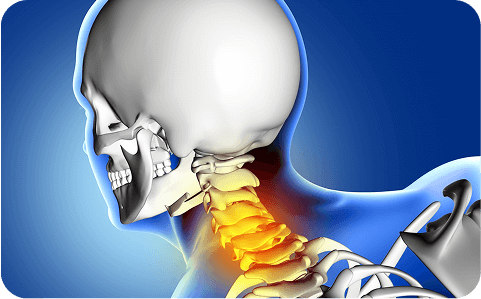

Stiffness, posture strain, facet pain when turning or looking down.

Migraine, tension, or cervicogenic headaches; occipital nerve blocks clarify the source.

Post-impact stiffness, muscle spasm, and loss of range of motion.

Arm pain, tingling, or weakness from compressed nerve roots.

Disc bulge or rupture pressing nerves; treated with epidurals and micro-decompression.

Canal narrowing leading to hand clumsiness, leg heaviness, or unsteady gait.